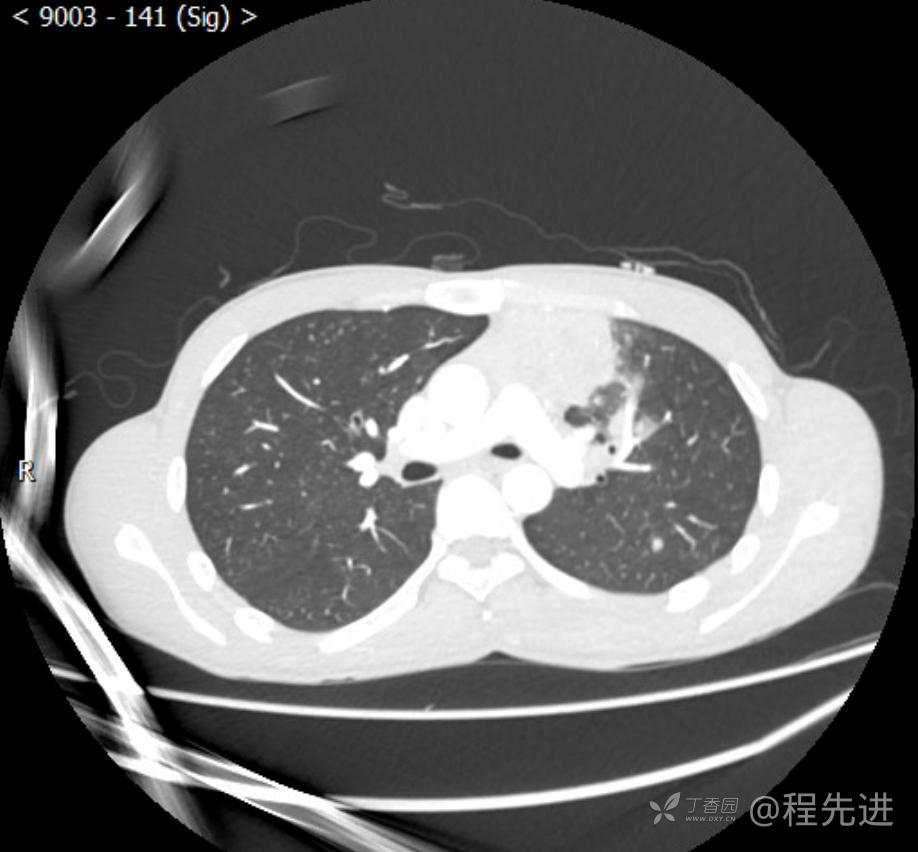

主诉:反复咳嗽1月,发现“纵隔”占位半月,乏力10余天。

现病史:患者1月前无明显诱因出现咳嗽,以夜间为著,伴有少量白痰,无发热,无胸痛、咯血,无痰中带血,未予重视,半月前外院行胸部CT检查发现“左前上纵隔”占位,未予进一步检查及治疗。近10余天自觉乏力,逐渐加重。